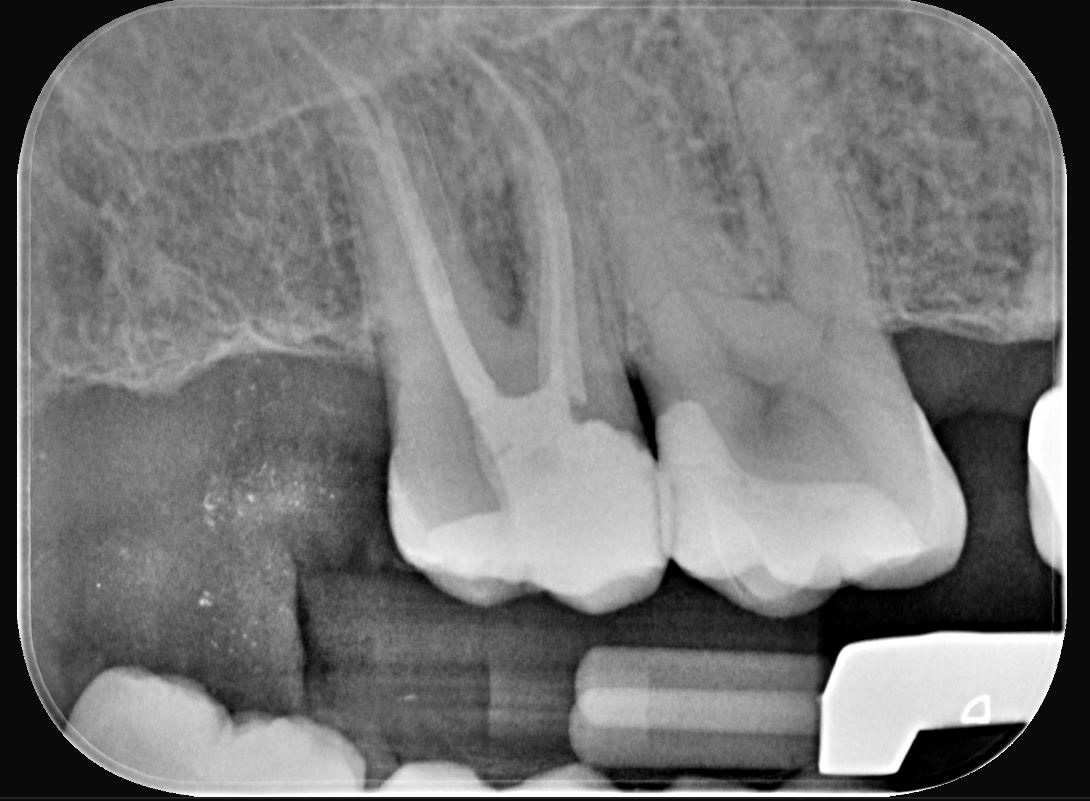

Una paziente di 44 anni si presenta alla nostra attenzione per la sostituzione di un vecchio restauro danneggiato. All’esame clinico si osserva la frattura della cuspide disto-palatina dell’elemento 1.6, associata a infiltrazione marginale di un restauro in composito incongruo. Le radiografie periapicali non evidenziano radiotrasparenze periapicali, ma mostrano possibili aree di demineralizzazione in zona marginale e all’interfaccia dente-restauro (1, 2, 3) (Figure 1-2).

Dopo la rimozione della diga di gomma, per le zone di contatto si procede a rifiniture interprossimali con strisce abrasive. Concluso il controllo occlusale, per il molaggio selettivo dei precontatti si utilizza una fresa a pallina in carburo di tungsteno. Seguono quindi rifinitura e lucidatura con gommini abrasivi diamantati. Alcune superfici ruvide dell’overlay vengono rifinite e lucidate con l’ausilio di dischetti abrasivi a grana fine e di gommini. Con i dischi in feltro si passa alla lucidatura a specchio impiegando una pasta non abrasiva all’ossido di cerio. Dopo 15 giorni, si eseguono controllo radiografico e verifica del restauro eseguito (Figure 16-18). La Tabella 1 riassume il protocollo clinico utilizzato in questo case report.